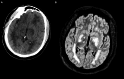

Severe malaria, caused by Plasmodium falciparum, poses a critical public health challenge, with cerebral malaria (CM) representing its most severe and life-threatening neurological manifestation. Defined by impaired consciousness (Glasgow Coma Score < 11) after the exclusion of other causes of encephalopathy, CM remains a critical condition with a mortality rate of 15-25% and long-term neurological sequelae in survivors. CM pathogenesis involves parasitized erythrocyte sequestration in cerebral microvasculature, immune hyperactivation, blood-brain barrier disruption, and cerebral edema, potentially leading to elevated intracranial pressure (ICP) and cerebral ischemia. These processes culminate in severe neurological injury, emphasizing the importance of ICP management in minimizing secondary brain damage. Neuromonitoring (NM) strategies, including invasive and non-invasive techniques, are critical yet underutilized in adults with CM due to limited evidence and logistical challenges. Treatment relies on antimalarial therapy, with intravenous artesunate as the first-line drug, supported by targeted interventions to manage seizures and systemic complications. Adjunctive therapies remain experimental, with no proven benefit in routine care. Emerging evidence from pediatric studies offers valuable insights, though significant gaps in adult-focused research persist. This review, which examines severe CM pathophysiology, clinical manifestations, and management, focusing on adult populations, underscores the need for tailored NM approaches, protocolized management strategies, and further investigation to improve outcomes in adults with CM, advocating for a multidisciplinary approach within the intensive care setting.